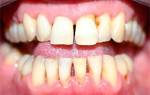

Фото 2. Слева – фото до процедуры по удалению зуба, справа видны последствия – изменение прикуса.

Фото 3. На фото видны изменения, к которым привели зубы мудрости, при этом остальные начали сдвигаться, торчать в разные стороны.

Изменение прикуса, расходятся нижняя и верхняя челюсти

Чаще всего после удаления восьмёрки остальные зубы начинают «расходиться» и «раздвигаться», что приводит к изменению прикуса.